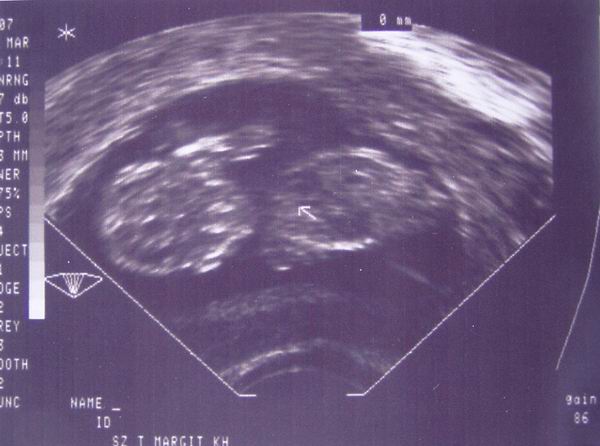

Pénteken megyek UH-ra, már nagyon várom